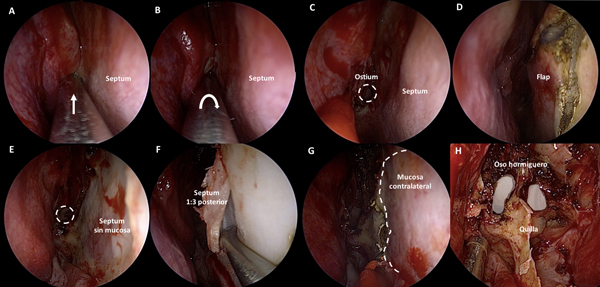

Se procede a la luxación hacia medial y desplazamiento hacia lateral de ambos cornetes inferiores. Luego, se coloca cotonoide embebido en vasoconstrictor entre el cornete medio y el septum nasal a cada lado. Acto seguido, con un disector de Cottle, se desplaza con delicadeza cada cornete medio hacia lateral. El cornete medio no debe ser resecado ni fracturado. Esta maniobra genera un corredor quirúrgico que permite el acceso al receso esfeno-etmoidal a cada lado (Figura 1 A-H).

Figura 1. Fase nasal: tratamiento de los cornetes. A-D: fosa nasal derecha. A-B: lateralización de cornete inferior derecho. C-D: lateralización de cornete medio derecho. E-H: fosa nasal izquierda. E-F: lateralización de cornete inferior izquierdo. C-D: lateralización de cornete medio izquierdo.

Figura 2. Fase naso-esfenoidal. A-B: identificación mediante palpación y apertura con maniobra rotacional del ostium esfenoidal. C-D: tallado del mini-rescue flap. E-F: septum denudado y desinserción osteo-cartilaginosa. G: exposición de mucosa contralateral luego de septectomía posterior; en línea de puntos se delimita el sitio de corte. H: rostro de oso hormiguero luego de exponer el rostrum esfenoidal.